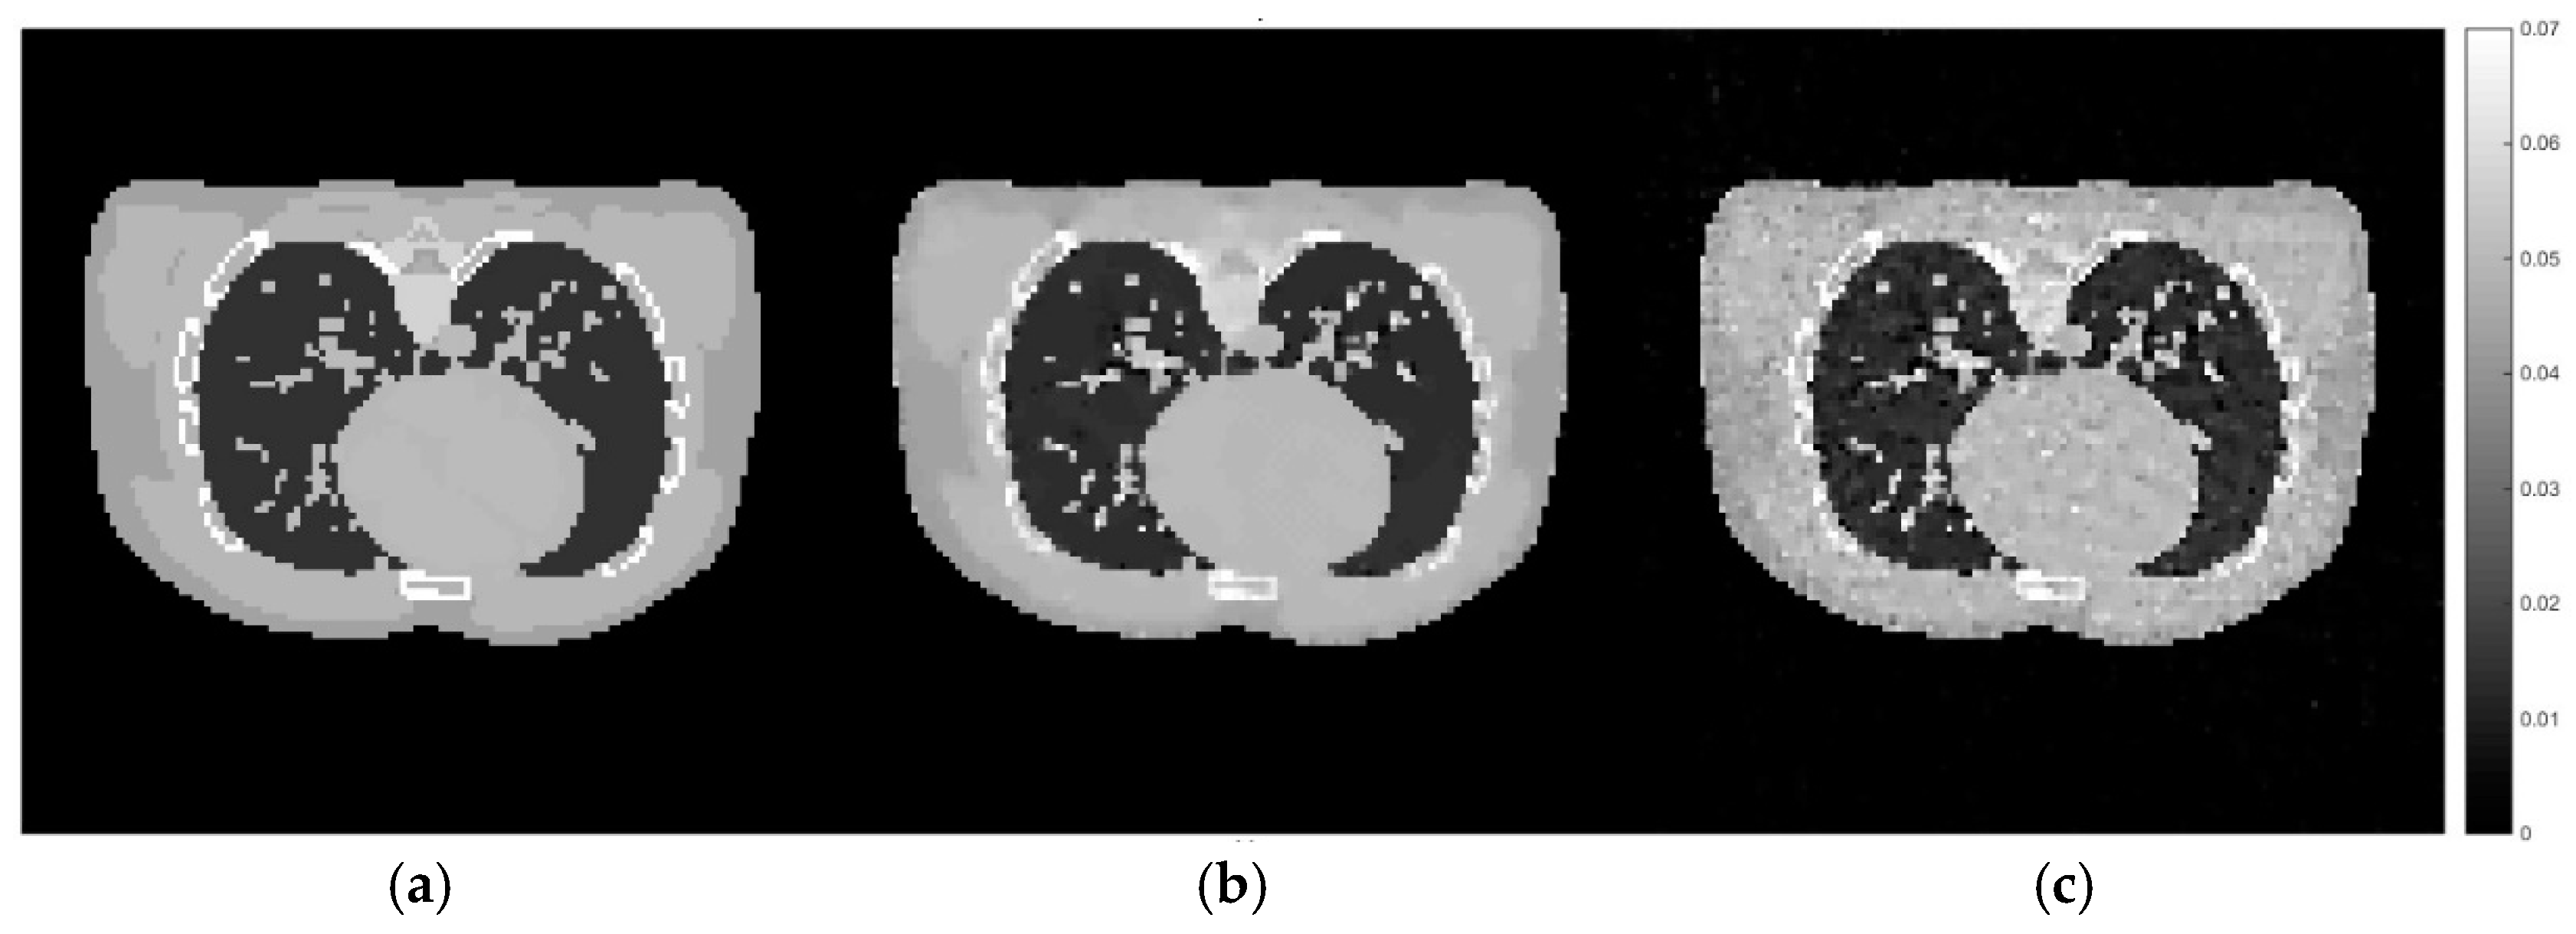

Figure 11.

Cross-sectional slices of the reconstructed images from the male phantom using the same sets of hyperparameter settings and the CGLS algorithm as applied to the training dataset previously. The display window is [0–0.07].

According to Figure 11, the reconstruction using the set of hyperparameters obtained from the training dataset still able to produce good quality of image, comparing to other methods. We then implement the proposed method directly to the projection simulated from the male phantom to further analyse the difference between these two cases. The cross-sectional slices are shown in Figure 12. The relative errors and the UQI, as well as the sets of hyperparameters used in each method are presented in Table 5.

Figure 12.

Cross-sectional slices of (a) the exact image of male phantom data, (b) the reconstruction from directly implemented the proposed method on the male phantom data, (c) the reconstruction using the hyperparameters obtained from the training stage.